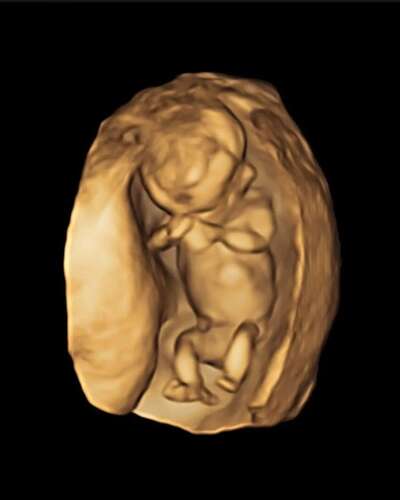

12+3 dagen met 3d foto van de echo, wat denken jullie?